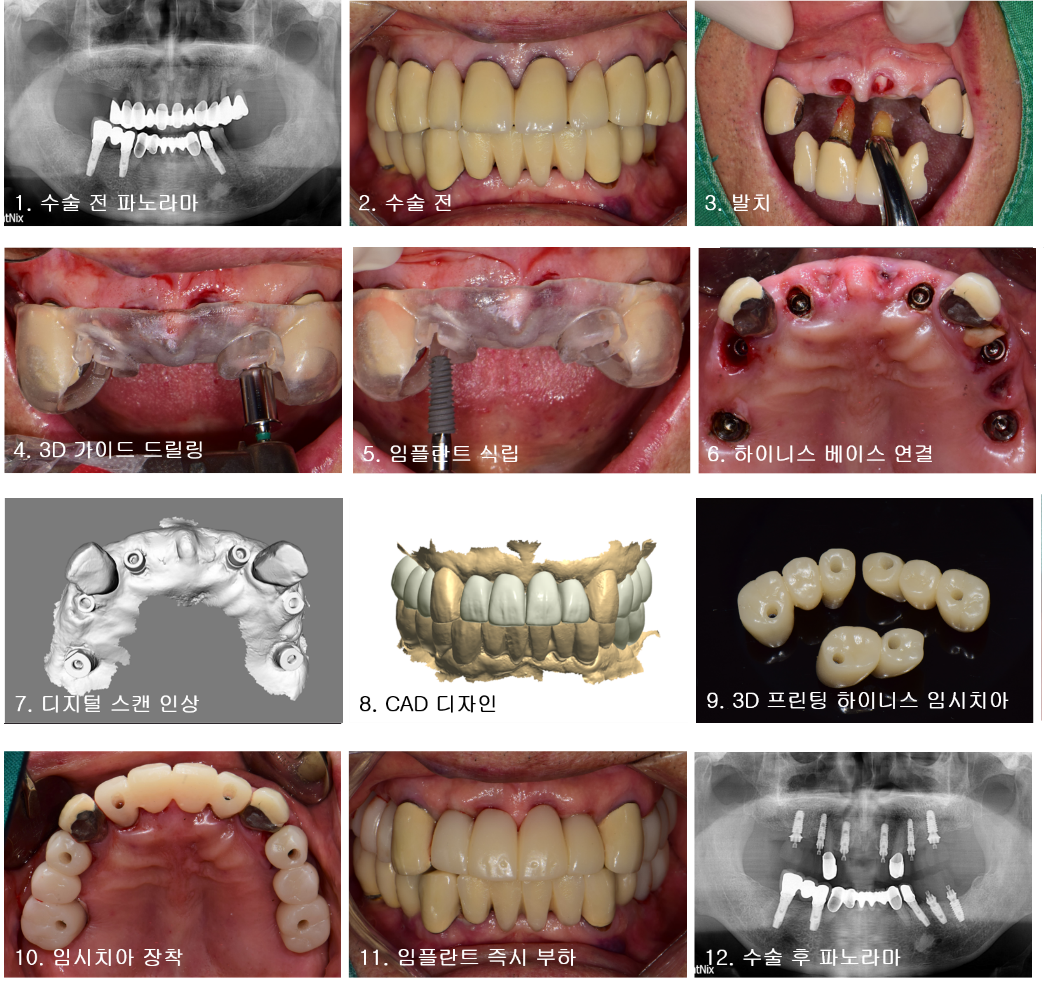

위쪽 증례에서 보듯이 하이니스 보철 시스템을 활용하여 Immediate implant placement 및 Immediateloading을 성공적으로 시행하였다. 임플란트 식립 직후 디지털 스캔인상을 채득하고 CAD 작업 후 3D 프린터로 즉시 수복물을 제작하였다.

수술 당일 임플란트 보철을 장착할 수 있으므로 심미성과 기능적인 측면에서 환자와 술자 모두 만족할 수 있었다.

하이니스 보철 시스템은 앞서 언급한 교합력 분산효과 외에도 스크루 유지형 보철이므로 임시 수복물의 형태 수정이 매우 용이하고 잔여시멘트에 의한 염증 발생을 우려할 필요가 없다.

이를 통해 심미적인 연조직 재형성과 안정적인 골치유가 가능하므로 최종보철 제작을 위한 최적의 환경을 구축할 수 있다.

Immediateloading 시 임상의 편리성을 위해 간편한 보철제작은 필수적 요건이라 생각된다.

하이니스 보철 시스템은 customized abutment 제작없이 디자인 파일의 3D 프린팅이나 PMMA 밀링만으로도 임시보철물 제작이 가능하므로 기존의 방식보다 Immediate/Early loading 편리하게 사용할 수 있다.